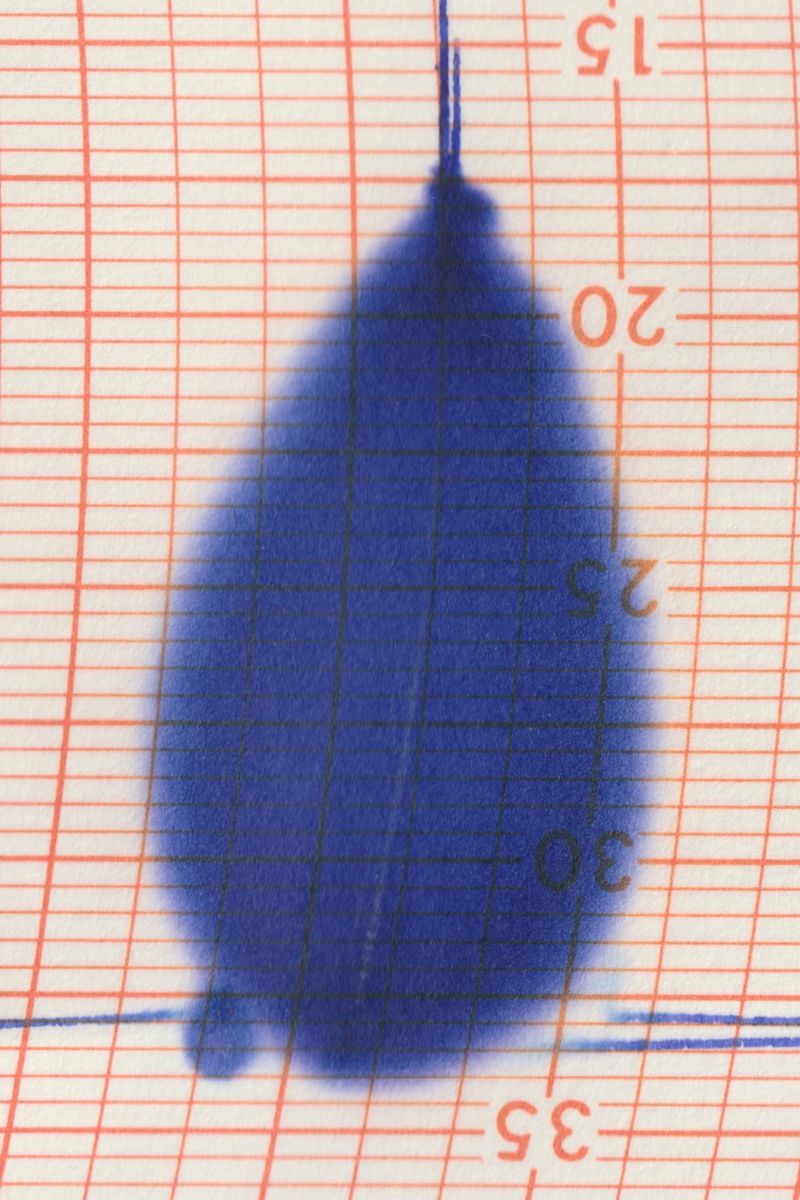

Collirio (Eye wash) is the attempt to demonstrate the non-absoluteness of visual experience, its nature as a situated, and yet, ambiguous act. It is the path that has allowed me to understand how my fears do not have roots in an unknowable place. The eye is not an unfathomable globe.

Collirio is the photographic project I presented for my BA degree at ISIA Urbino. I designed a book (22x29.5cm, 160pages) with text pages and transparent paper inserts and a printed canvas-like dust jacket. A photographic reference scale ruler has been applied on the cover of each of the copies.